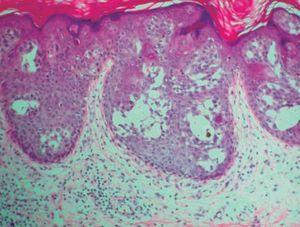

Presentamos el caso de una mujer de 88 años con varias lesiones en la región submamaria derecha, que habían permanecido estables durante más de 40 años, que refiere un rápido crecimiento y ulceración de una de ellas en el último año. En la exploración mostraba, bajo la mama derecha, una lesión tumoral de 7 cm de diámetro, de consistencia firme, superficie queratósica en periferia y ulcerada en el centro y exudación serosa maloliente. Adyacentes a ella se observaban varias lesiones tumorales de menor tamaño, con una superficie aterciopelada, de coloración eritemato-pardusca, y con una distribución lineal (fig. 1). No se palparon adenopatías loco-regionales. El estudio analítico completo, así como las radiografías de tórax, electrocardiograma, mamografía bilateral y ecografía axilar derecha, fueron rigurosamente normales. Se realizó una biopsia incisional de la lesión tumoral de mayor tamaño y otra biopsia de una de las lesiones adyacentes. En el primer caso, la tinción de hematoxilina-eosina mostró islotes irregulares anastomosados compuestos por células tumorales intraepidérmicas, algunas de ellas pigmentadas, con un citoplasma más claro que los queratinocitos circundantes. Se observaron abundantes células atípicas con núcleos grandes, irregulares e hipercromáticos dentro de las masas tumorales. En algunas secciones se podían ver espacios quísticos dentro de estos nidos de células basaloides. La epidermis presentaba hiperqueratosis, focos de paraqueratosis y acantosis irregular (fig. 2 A y B). La biopsia de la lesión de menor tamaño mostró nidos bien definidos de células cuboidales uniformes que poseían núcleos basofílicos, redondeados y no atípicos, con presencia de estructuras quísticas en su seno (fig. 3). El citoplasma de las células tumorales contenía gránulos PAS positivos en ambos casos. Las tinciones inmunohistoquímicas demostraron que los islotes tumorales se teñían con anticuerpos monoclonales frente a las citoqueratinas AE1/AE3, 34betaE12 y EMA, y no presentaron reactividad para las citoqueratinas 7, 20, CAM5.2, CEA y GCDFP15. Se realizó el diagnóstico de hidroacantoma simple maligno (HSM) sobre un hidroacantoma simple (HS) de distribución lineal; el tumor maligno ulcerado fue extirpado quirúrgicamente. Un año y medio después del diagnóstico, la paciente permanece asintomática y sin evidencia de metástasis a distancia en los seguimientos realizados, que incluyeron una exploración física trimestral y una analítica de sangre, una radiografía de tórax y una ecografía abdominal semestrales.

Figura 3. Islotes bien definidos de células tumorales no atípicas formando estructuras quísticas (hematoxilina-eosina, x40).